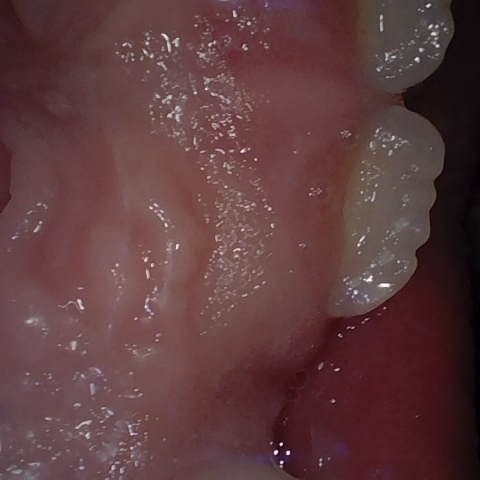

Annotated as "Good"